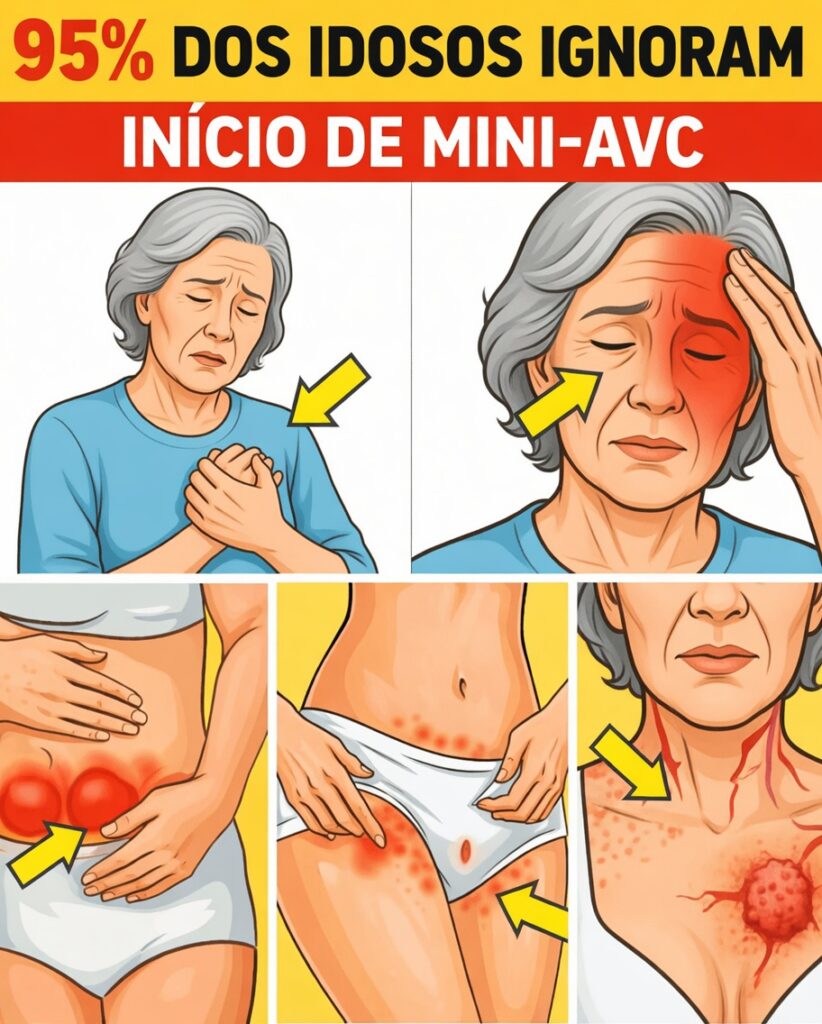

10 sintomas de mini AVC silencioso que quase ninguém nota depois dos 60

Em muitos casos, esses episódios aparentemente inofensivos podem ser sintomas de mini AVC silencioso, indicando um risco mais sério à frente se não forem avaliados. Eles se confundem facilmente com “coisas da idade”, alimentando o medo de que algo grave esteja se desenvolvendo sem ser percebido e possa roubar seu estilo de vida ativo.

A parte positiva é que, ao reconhecer cedo os sintomas de mini AVC silencioso, você ganha tempo para buscar ajuda médica adequada. A seguir, descubra os 10 sintomas de mini AVC silencioso mais ignorados, com destaque especial para o sinal surpreendente que quase todo mundo deixa passar, no item 4.

10 sintomas de mini AVC silencioso frequentemente ignorados

Abaixo estão os 10 sinais mais subestimados. Se você se reconhece em algum deles, especialmente se os episódios surgem de repente e passam rápido, vale conversar com seu médico.

5. Dormência ou formigamento que vai e vem em apenas um lado do corpo

Aparece de repente uma sensação de “agulhadas” ou dormência no rosto, braço ou perna de apenas um lado, que some em pouco tempo. Esse tipo de dormência unilateral é considerado um dos principais sintomas de mini AVC silencioso, especialmente em pessoas acima de 60 anos, de acordo com a American Stroke Association.

É muito comum explicar esses episódios como “má circulação”, “posição errada ao dormir” ou “membro que dormiu”. Porém, se o formigamento surge sem motivo claro, acomete sempre o mesmo lado e se repete, isso pode indicar um problema vascular cerebral transitório.

2. Queda momentânea de um lado do rosto ou sorriso torto

Ao falar ou sorrir diante do espelho, você percebe que um lado do rosto parece descer ou ficar mais “mole”, mas alguns minutos depois tudo volta ao normal. Essa fraqueza facial temporária é um dos sinais clássicos usados no teste FAST (Face, Arms, Speech, Time) para identificar AVC – e também pode aparecer em mini AVC silencioso.

Como o rosto volta rapidamente ao normal, muitas pessoas atribuem o episódio a cansaço ou a ter “dormido em posição estranha”. No entanto, uma assimetria súbita – um sorriso torto, pálpebra que cai, cantos da boca desiguais – indica possível comprometimento de áreas cerebrais que controlam os músculos da face.

Mesmos que dure pouco, esse é um dos sintomas de mini AVC silencioso que mais apontam para risco de um AVC completo no futuro. Por isso, vale registrar o horário, tirar uma foto se possível e relatar ao médico.

1. Fraqueza súbita em um braço, perna ou em todo um lado do corpo

O sintoma número 1, frequentemente ligado ao “AVC clássico”, também pode surgir de forma breve em um mini AVC silencioso: de repente, um braço ou uma perna perdem força, segurando objetos ou caminhando se torna difícil, e alguns minutos depois tudo melhora.

Essa fraqueza unilateral súbita é um dos sinais mais importantes de alerta. Pode ser algo como deixar cair uma xícara sem entender por quê, arrastar levemente um pé ao andar ou não conseguir levantar o braço como de costume.

Mesmo que a força volte, isso pode indicar que uma área do cérebro ficou temporariamente sem fluxo sanguíneo adequado. Ignorar esse tipo de sintoma de mini AVC silencioso é abrir espaço para um AVC mais grave ocorrer depois, muitas vezes sem aviso adicional.